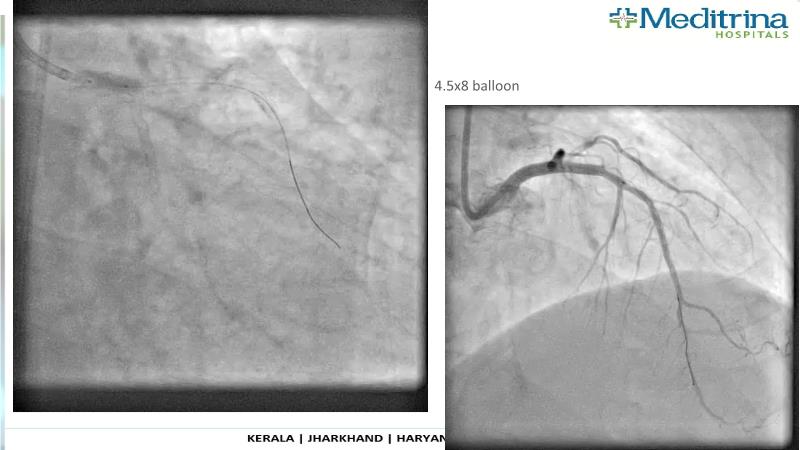

- To define the use of OCT in PCI of complex coronary lesions